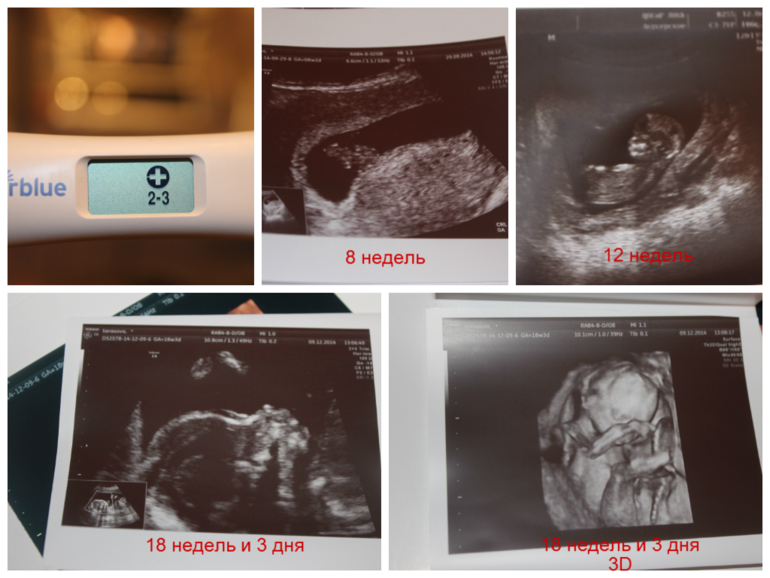

А это коллажик малыша))

Сейчас самое классное состояние пузика! Он уже хорошо всем заметен, но ещё совсем тебе не мешает! Наслаждайся)))Ой, Захарка такой худышик на 3D узишном фоте))))

Да, наслаждаюсь во всю))а Захар худенький, всего 200 с лишним грамм, скоро будем слонятами, придет наше время, главное мне все таки знать меру — не переедать и не кушать вредностей)))